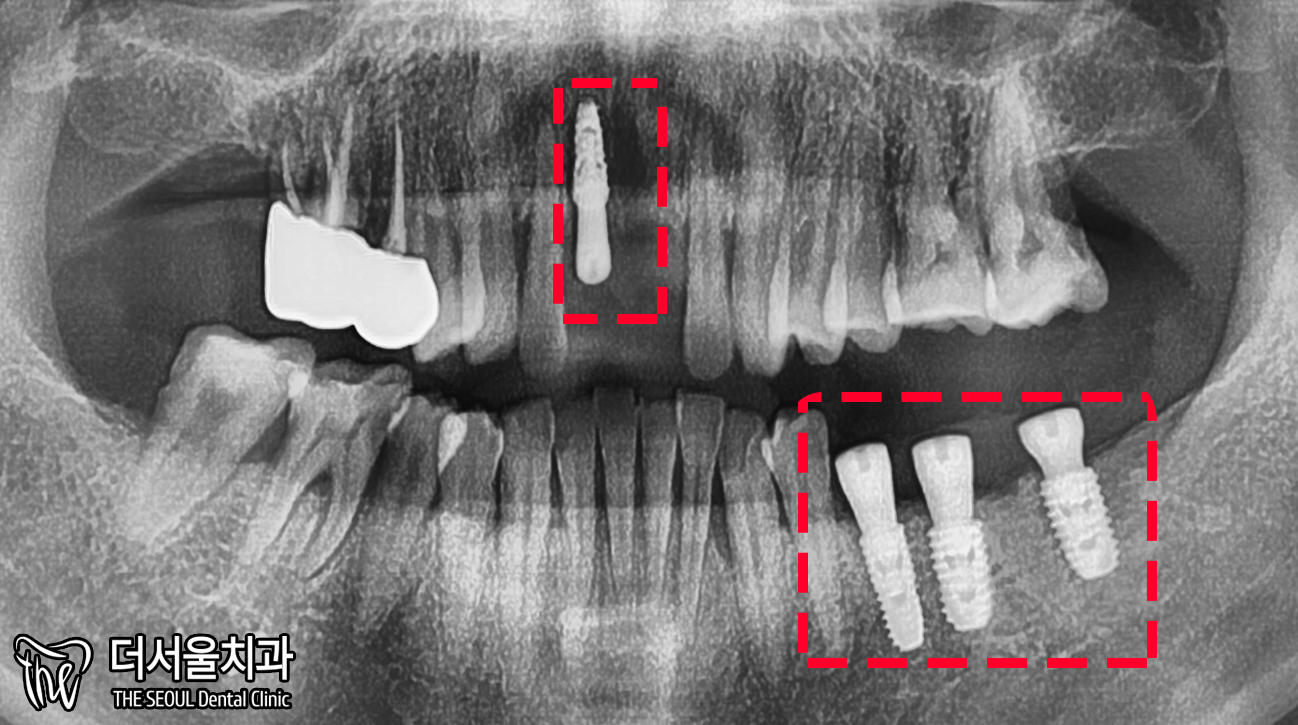

4. 과정

짜놓은 계획에 맞춰

픽스처를 심어줬습니다.

잇몸에 굳이 묻어둘 필요없이

‘힐링 어버트먼트’를 연결할 정도로

뼈 상태는 좋았습니다.

엑스레이로 확인했을지라도

3D CT를 촬영하여 한번 더 체크해줍니다.

원하는 위치에 잘 심어졌네요 ^^

3개월 뒤, 골결합이 잘 이뤄짐을 확인했습니다.

엑스레이로 한번 더 체크했을 때도

뼈와 잘 붙었습니다.